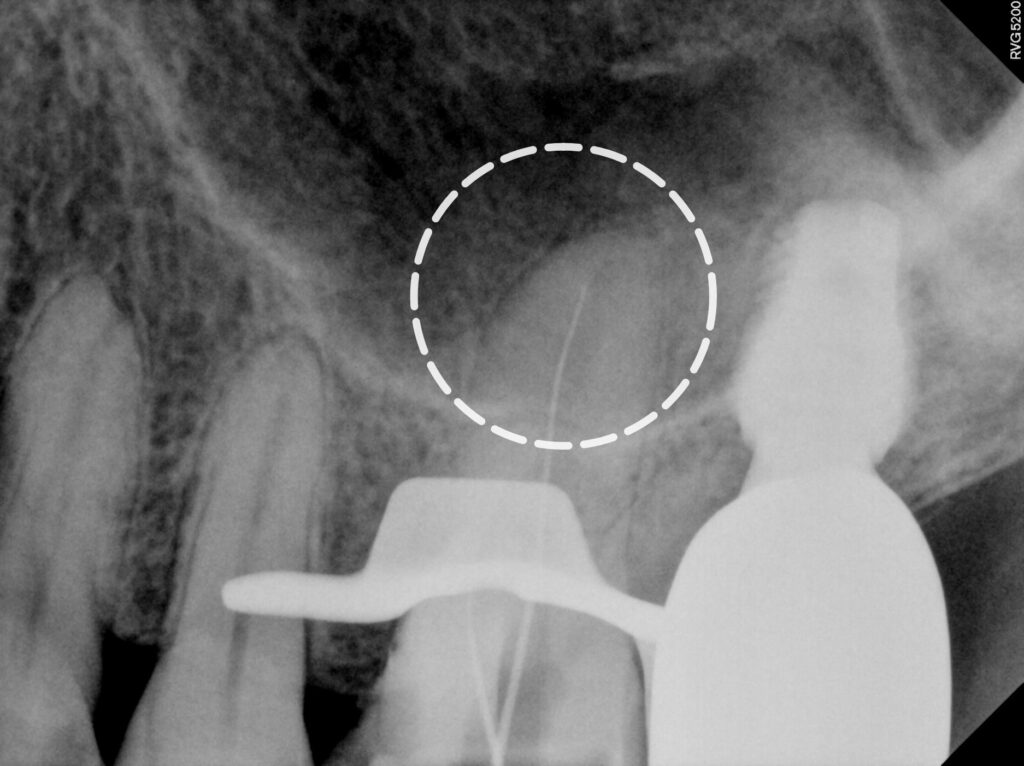

2025.05.12

여러 차례의 소독 과정을 거쳐

세균을 완전히 제거한 후

근관 충전재로 빈 공간을 채워

세균의 재침입을 방지합니다.